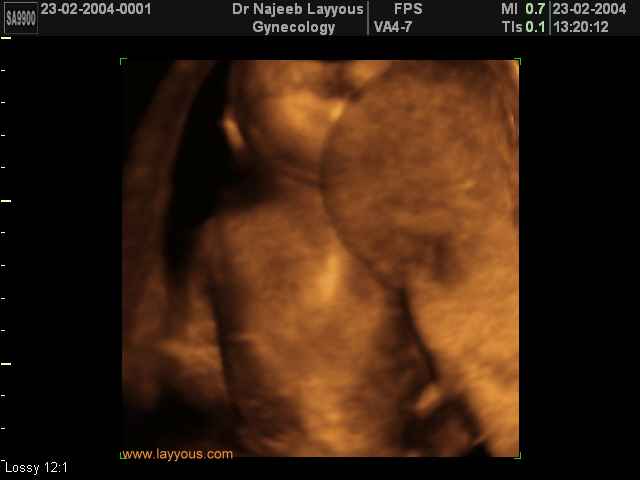

صور لأعضاء الجنين بجهاز الموجات فوق صوتية ثلاثي الأبعاد | الدكتور نجيب ليوس

صور لأعضاء الجنين بجهاز الموجات فوق صوتية ثلاثي الأبعاد